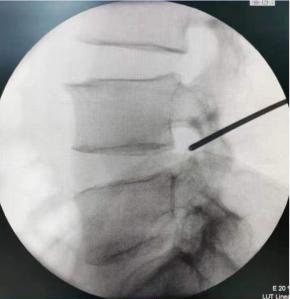

• 不同入路脊柱内镜手术治疗L4/5节段脱垂型腰椎间盘突出症的疗效比较

摘要:目的 观察经椎间孔入路内镜下腰椎间盘切除术(TELD)和经椎板间入路内镜下腰椎间盘摘除术(IELD)治疗L4/5节段脱垂型腰椎间盘突出症(LDH)的临床疗效。方法 回顾性分析2020年11月-2022年11月该院采用脊柱内镜手术治疗的75例L4/5节段脱垂型LDH患者的临床资料。根据手术入路的不同,将患者分为TELD组(53例)和IELD组(22例)。比较两组患者的手术情况和术后疗效。结果 与TELD组比较,IELD组的手术时间明显缩短,术中透视次数明显减少,差异均有统计学意义(P < 0.05);两组患者住院时间和并发症发生率比较,差异均无统计学意义(P > 0.05)。所有患者术后均获得12~19个月的随访。两组患者末次随访时的视觉模拟评分法(VAS)评分和Oswestry功能障碍指数(ODI)明显低于术前,且IELD组明显低于TELD组,差异均有统计学意义(P < 0.05)。按照突出物和神经根的不同位置进一步分析,两组肩上型患者(TELD组10例,IELD组6例)末次随访时的VAS评分和ODI明显低于术前,且IELD组末次随访时的VAS评分明显低于TELD组,差异均有统计学意义(P < 0.05);两组腋下型患者(TELD组8例,IELD组16例)末次随访时的VAS评分和ODI明显低于术前,且IELD组明显低于TELD组,差异均有统计学意义(P < 0.05);35例肩前型患者经TELD术后,末次随访时的VAS评分和ODI明显低于术前,差异有统计学意义(P < 0.05)。按照突出物的不同Lee分区进一步分析,两组Lee Ⅲ区患者(TELD组44例,IELD组10例)末次随访时的VAS评分和ODI明显低于术前,且IELD组的ODI明显低于TELD组,差异均有统计学意义(P < 0.05);两组Lee Ⅳ区患者(TELD组9例,IELD组12例)末次随访时的VAS评分和ODI明显低于术前,且IELD组明显低于TELD组,差异均有统计学意义(P < 0.05)。结论 采用TELD和IELD治疗L4/5节段脱垂型LDH,均可获得较满意的减压效果,但IELD的手术时间相对较短,X线透视次数较少,且对肩上型、腋下型、Lee Ⅲ区和Lee Ⅳ区的减压效果更有优势。